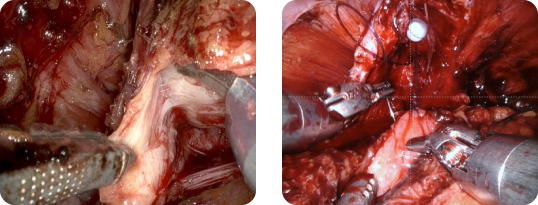

ロボット支援前立腺全摘除術

ロボット支援腎部分切除術